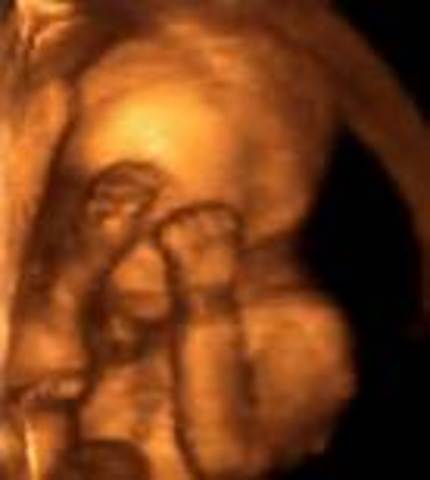

• Week 11

Week 11

•The fetus CRL is about 1.5 inches (35mm) in size.

•The fingers and toes have completely separated.

•The taste buds are starting to develop.

•Baby has tooth buds, the beginning of the complete set of 20 milk teeth.

•Baby can swallow and stick out his or her tongue.

•Whole body except tongue is sensitive to touch.

•Cartilage now calcifying to become bone.

•If it is a boy, the testicles are starting to produce the testosterone hormone website baby2see